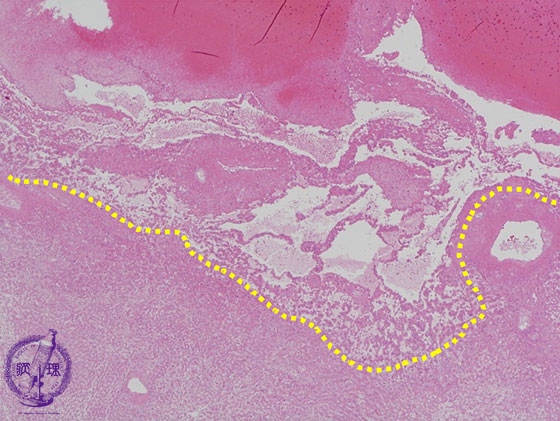

- ★(14)Angiosarcoma of the liver

Microscopic image (HE stain, low power): The boundary (yellow dashed line) between tumor and non-neoplastic liver is unclear.